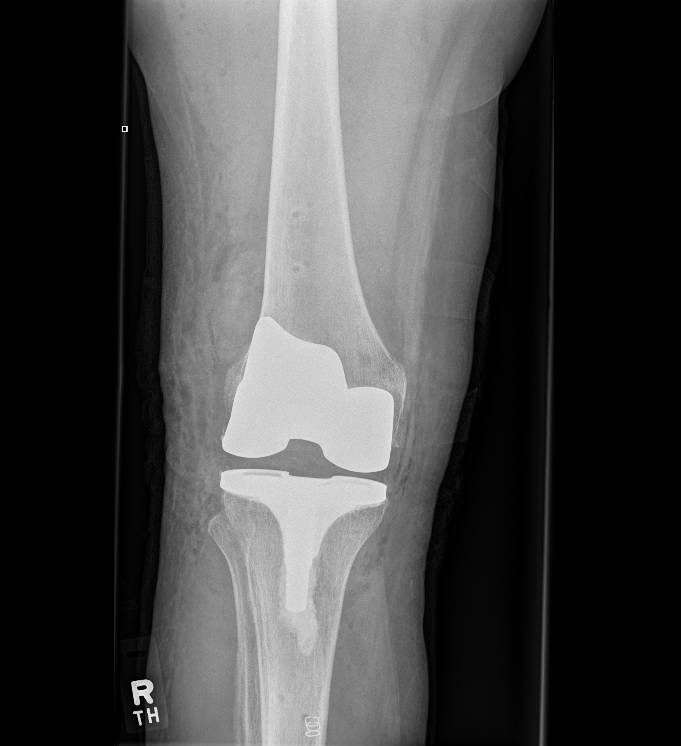

Total Knee Replacement

When more than one compartment (medial, lateral, patella) of the knee wears out and non-operative treatment options have failed a total knee replacement is required.

If the arthritis within the knee affects more than one compartment then a total knee replacement may be recommended.

In a conventional knee replacement, instruments are used to perform the bony cuts and restore the knee back to its original (mechanical) position. This involves releasing some of the ligaments and soft tissues around the knee so that a balanced, full range of motion is achieved at the end of the surgery.

Through a midline incision the surfaces of the bone can be replaced. The femoral component is a smooth metal component of varying sizes, which fits over the end of the femur. The tibial component consists of a metal base plate that sits on top of the tibia and a polyethelene (plastic) insert that fixes onto the tibial component. The patella surface may be replaced if it is worn. The implants are positioned and fixed to the bone using bone cement.